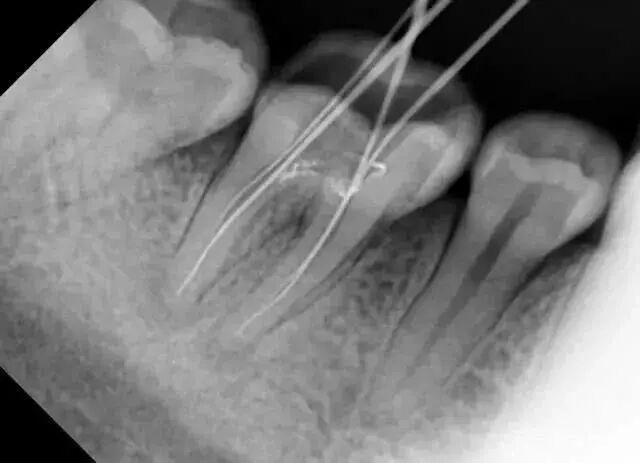

比如,当拔除下颌智齿时,仅凭口内检查无法发现它离神经管的位置

常见的牙科放射检查包括曲面体层片( 全景片 )、小牙片、头颅正侧位片、全头颅 CT、锥形束 CT( CBCT )等。由于牙齿下部隐藏在牙槽骨中,口腔医生要了解牙齿的整体情况就需要拍摄全景片;

要了解个别牙根及周围变化,则选择拍摄小牙片。医生要判断牙槽骨是否符合种植条件,或者了解埋伏阻生齿的三维位置以及其他颌骨内病变组织的形态大小时,则需要进一步拍摄 CBCT 。